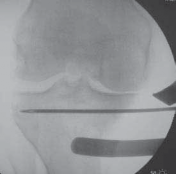

2. Before the osteotomy is performed, an intraoperative mechanical axis view should be obtained, using either

the Bovie cord or the alignment rod found in the osteotomy set.

TECHNIQUES

4. Using fluoroscopy, the alignment rod is placed at the center of the femoral head (

TECH FIG 3A

) and then at the center of the ankle joint (

TECH FIG 3B

).

A B F

1 cm below joint line

Osteotomy guide instrument

Sartorius fascia and ACL

D E TECH FIG 3•A.

Fluoroscopic image of alignment rod through femoral head.

B.

Fluoroscopic image of the alignment rod in the center of the ankle.

C.

The subsequent location of the alignment rod in the knee. This initial mechanical axis must be corrected. It should match with the preoperative planning.

D.

Initial guide pin from medial to lateral and parallel to the joint line. The pin is placed approximately 1 cm distal to the joint line.

E.

Osteotomy guide pin assembly over the initial guide pin. The angle of the guide pin assembly is changed so that the guide pins are just superior to the tibial tubercle. Two pins are drilled from medial to lateral along the osteotomy line to intersect the initial guide pin 1 cm from the lateral cortex.

F.

Fluoroscopic image verifying the two guide pins placed from medial to lateral using the osteotomy guide pin assembly. Note how in this view, which is parallel to the joint surface, the two pins are superimposed on one another, thus verifying that they, too, are parallel to the joint surface.

White arrow,

guide pin assembly;

black arrow,

osteotomy guide pins;

black arrowhead,

initial guide pin.

1. The subsequent location of the alignment rod in the coronal view of the knee is the intraoperative location of the mechanical axis (

TECH FIG 3C

2. These radiographs are saved for later comparison.

1. A guide pin is placed from medial to lateral across the proximal tibia, 1 cm distal to the joint, and parallel to the joint surface.

1. The tip of the guide pin should be just proximal to the level of the fibula. The location of this guide pin should be verified with fluoroscopy (

TECH FIG 3D

2. The osteotomy guide pin assembly is then inserted onto the guide pin (

TECH FIG 3E

). The guide pin assembly acts on the same concept as an ACL tibial aiming guide, placing the subsequent guide pins at the proper angle and oriented to the tip of the previous guide pin placed parallel to the joint line.

3. A parallel guide sleeve is then inserted onto the osteotomy guide pin assembly.

1. Not only can the osteotomy guide pin assembly determine the angle of the cut in the coronal plane, but it

also has the ability to rotate in the sagittal plane to reproduce the anterior-to-posterior tibial plateau slope accurately. This can be helpful in special situations (eg, PCL or ACL deficiency) in which further alterations in the tibial slope may be necessary (eg, a biplane osteotomy).

5. The angle of the guide pin assembly in the coronal plane is set so that the guide pins will enter the proximal tibia above the tibial tubercle.

5. When acceptable, two further guide pins are drilled from medial to lateral along the orientation of the osteotomy cut. Their position is verified with fluoroscopy (

TECH FIG 3F

6. The parallel guide sleeve, guide pin assembly, and initial guidewire parallel to the joint line are now removed.